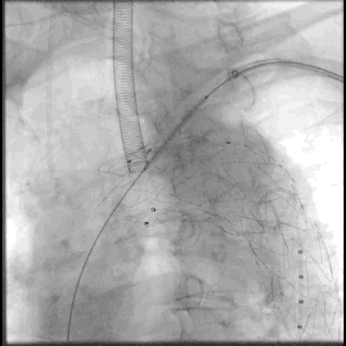

6. 最终造影:主动脉弓部瘤病变显影消失,主体支架形态良好,分支支架通畅,左椎动脉显影良好。

泥鳅导丝怎么用符伟国/王利新教授团队:0.035"普通泥鳅导丝进行胸主动脉弓上分支原位开窗的病例分享_https://www.jmylbn.com_新闻资讯_第24张

LAO位置最后造影

泥鳅导丝怎么用符伟国/王利新教授团队:0.035"普通泥鳅导丝进行胸主动脉弓上分支原位开窗的病例分享_https://www.jmylbn.com_新闻资讯_第25张

头向血流良好